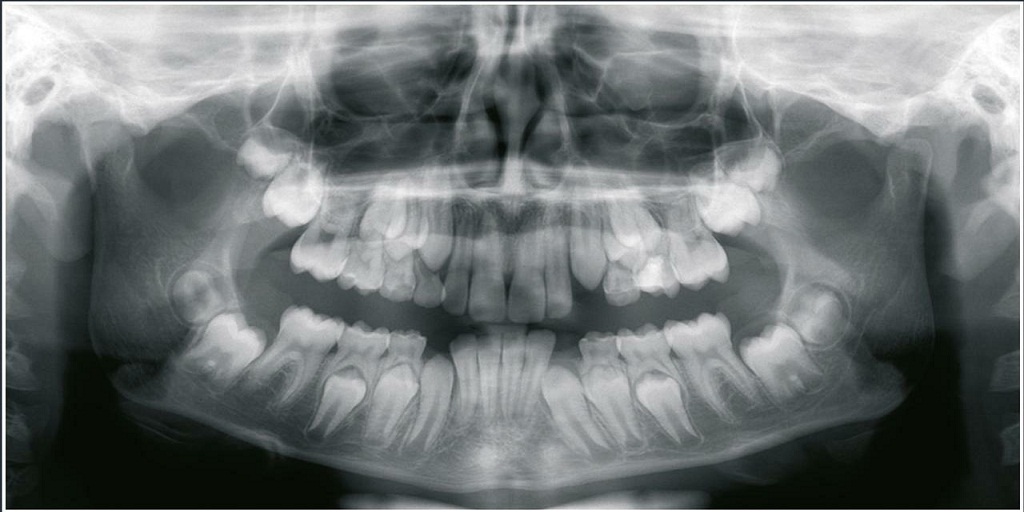

Dental imaging equipment is a necessity for almost all dental professionals. These machines assist in properly diagnosing and treating patients in a variety of ways. There are two common and modern dental imaging machines: panoramic X-ray and CBCT. Panoramic X-ray machines provide 2D images, while dental CBCT provide 3D images and most times 2D images, too.

Panoramic X-rays have several common applications, such as treatment planning for dentures, braces, extractions, and implants. General dentists can typically use a standard panoramic. Contrastingly, specialized applications (implants, orthodontics, and endodontics) sometimes require additional imaging capabilities, which could include a CBCT or cephalometric attachment.